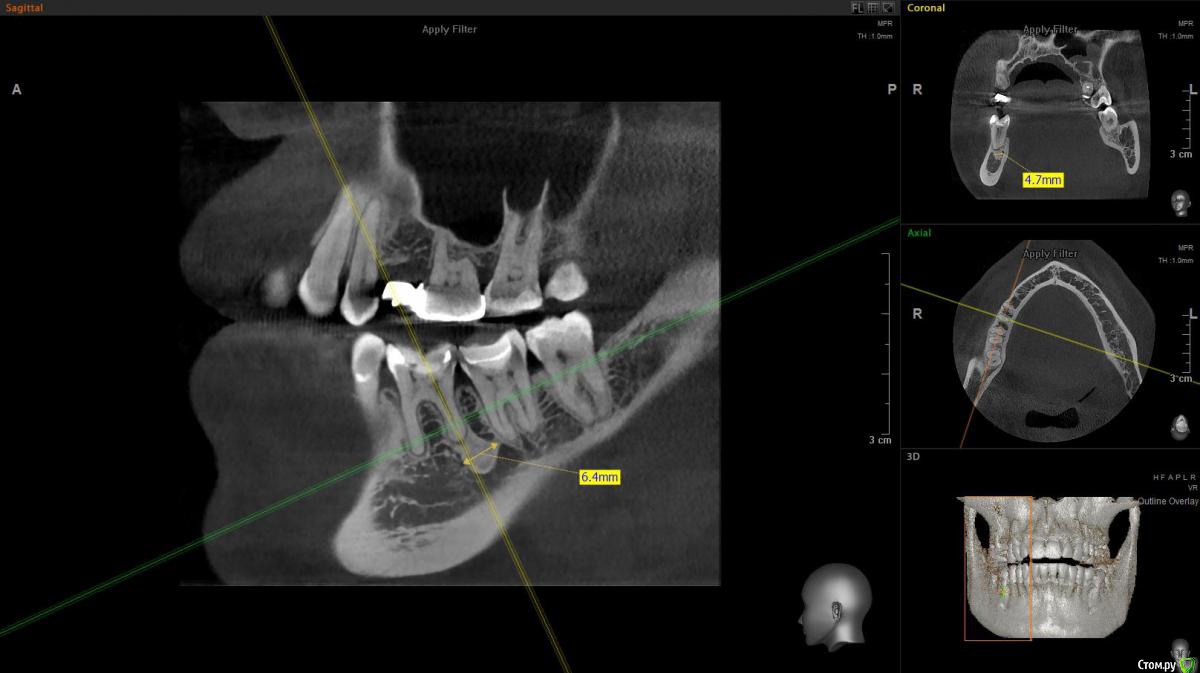

Turalyon Опубликовано 25 февраля, 2020 Поделиться Опубликовано 25 февраля, 2020 Добрый вечер, коллеги. Пациентка 1974 г. р обратилась с жалобами на боль при жевании.Зуб 46 лечен 2 мес. назад по поводу кариеса. Перкуссия +, пальпация в области переходной -, холодовой тест +, чувствительность проходит секунд через 5. В периапикальной имеется затемнение. Без гистологии окончательный диагноз не поставить, однако я предполагаю, что это остеома.Если что, могу кинуть ссылку на кт. Каково ваше мнение касаемо участка затемнения у апекса 46 зуба? 1 Ссылка на комментарий

krokomot Опубликовано 25 февраля, 2020 Поделиться Опубликовано 25 февраля, 2020 Это не остеома, а компактное вещество, вариант строения или аномалия. Ссылка на комментарий

Lodkin666 Опубликовано 26 февраля, 2020 Поделиться Опубликовано 26 февраля, 2020 Эностоз, участок более плотной кости. Забудьте про него. 1 Ссылка на комментарий